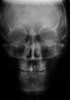

Fig 15. Postsurgical lateral (Fig 15) and posteroanterior (Fig 16) cephalometric x-rays, along with a panoramic x-ray (Fig 17). On the lateral cephalometric and panoramic x-rays, a robust .045-in transpalatal arch can be seen, which was used postsurgically to maintain the transverse correction achieved from the two-piece Le Fort 1 procedure.

Figure 15

Fig 16. Postsurgical lateral (Fig 15) and posteroanterior (Fig 16) cephalometric x-rays, along with a panoramic x-ray (Fig 17). On the lateral cephalometric and panoramic x-rays, a robust .045-in transpalatal arch can be seen, which was used postsurgically to maintain the transverse correction achieved from the two-piece Le Fort 1 procedure.

Figure 16

Fig 17. Postsurgical lateral (Fig 15) and posteroanterior (Fig 16) cephalometric x-rays, along with a panoramic x-ray (Fig 17). On the lateral cephalometric and panoramic x-rays, a robust .045-in transpalatal arch can be seen, which was used postsurgically to maintain the transverse correction achieved from the two-piece Le Fort 1 procedure.

Figure 17